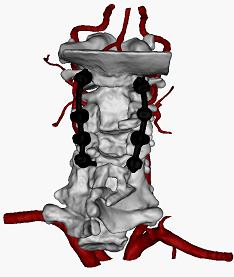

于是,吴超团队基于患者的颈椎三维模型,模拟置入颈椎椎弓根螺钉,并设计导航模板进行3D打印,术中结合骨科机器人导航,精准置入了颈椎椎椎弓根螺钉。

颈椎后路经椎弓根螺钉置入术长期以来被誉为脊柱外科手术中的“皇冠手术”,难度非常大;骨科中心联合3D打印导板和骨科手术机器人在该类高难度手术中的应用,综合抓取两种技术的优势,同时解决了机器人在跨节段固定置钉的漂移和下颈椎内倾角度较大导致的置钉困难等关键技术难题,简化了颈椎后路长节段固定的手术流程,缩短了患者的治疗过程,同时保证了置钉的安全性和准确性,极大减轻了患者的病痛和心理负担。

此外,本次手术也同时用到了我院新引进的全透视碳纤维手术床,该手术床可以保证患者在三维CT监视下安全完成颈椎螺钉植入手术。我院骨科中心作为四川省重点学科,配备有第三代骨科手术机器人、术中三维CT机、全碳纤维手术床等设备,硬件水平居川南领先位置。在先进设备支撑下,骨科中心团队完成了本次的全国首例机器人联合3D打印技术辅助颈椎手术。